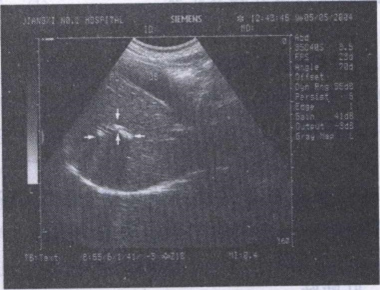

34.男,48岁,血吸虫疫区接触史,肝区胀痛,脾肿大。结合超声声像图,诊断为()